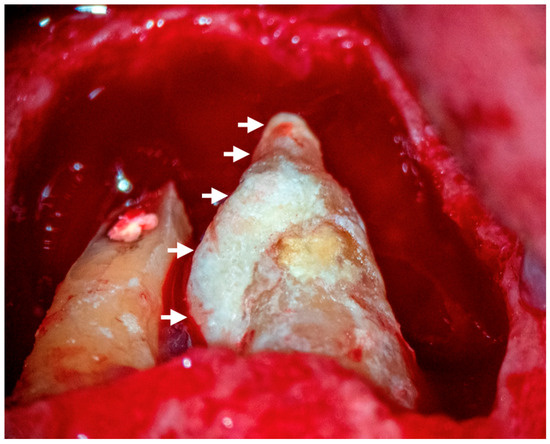

3.1.4. Extraradicular Biofilm and Calculus Formation

4.1. Etiology

4.4. Treatment of the Extraradicular Infection